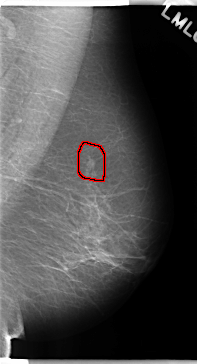

C_0188_1.RIGHT_MLO

FILE: C_0188_1.LEFT_MLO.OVERLAY

TOTAL_ABNORMALITIES 1

ABNORMALITY 1

LESION_TYPE MASS SHAPE OVAL MARGINS SPICULATED

ASSESSMENT 5

SUBTLETY 5

PATHOLOGY MALIGNANT

TOTAL_OUTLINES 1

BOUNDARY